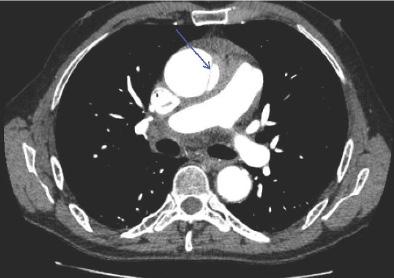

361 Painless Aortic Syndrome in a Patient with Syncope and Globus Sensation: A Case Report

G Rosenfeld-Barnhard, JR Jackson, KA Mendez, KE Schreyer

372 Contrast Agent Pooling in the Descending Aorta Due to Severe Heart Failure

Y Maezawa, K Nagasaki, H Kobayashi, S Sakai, T Irie